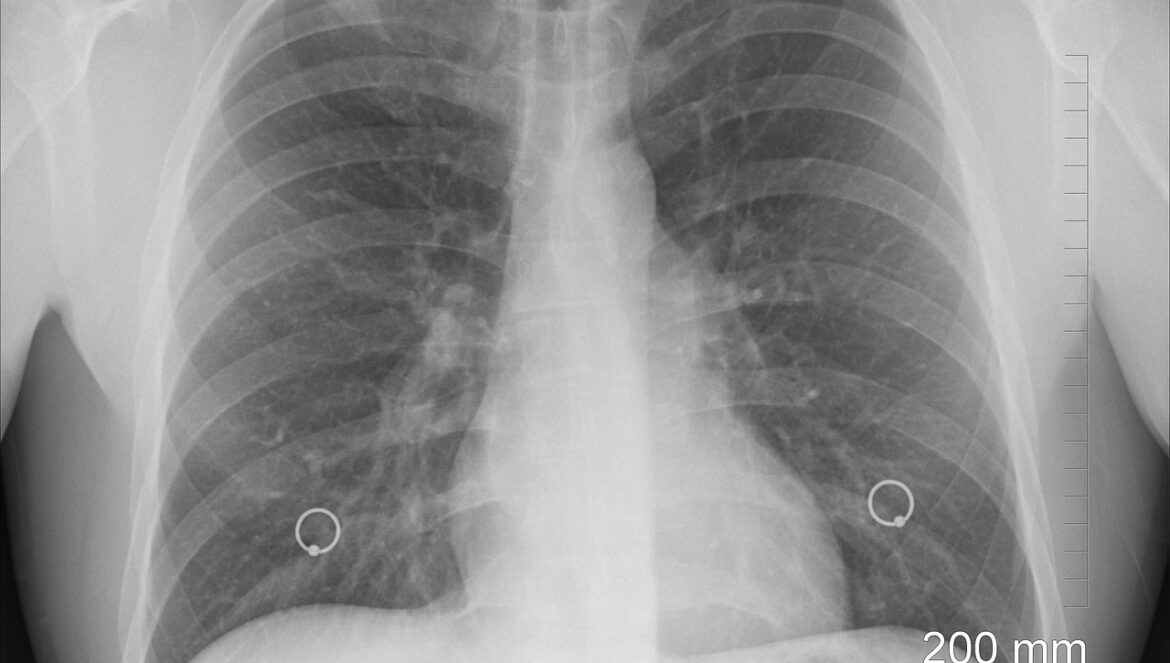

Карцином плућа представља водећи узрок смртности од свих малигнитета како у свету, тако и у Србији, док број оболелих расте сваке године, а према подацима Института за јавно здравље “Др Милан Јовановић Батут” за 2022. годину од ове малигне болести годишње оболи 6.500, а премине више од 5.000 особа. “То практично значи да у Србији … Настави са читањем Од карцинома плућа у Србији свака два сата премине једна особа!